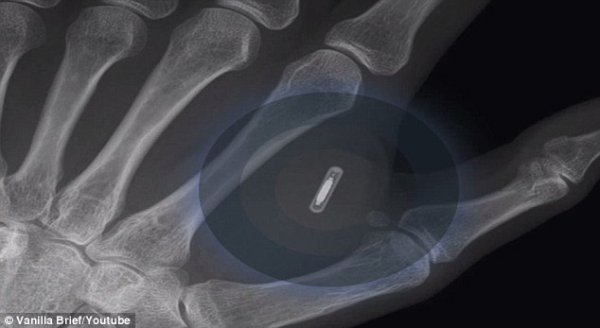

- 等不及了:为了iPhone 6,澳男子手中植入NFC标签

- 时间:2014-09-09 11:58:47